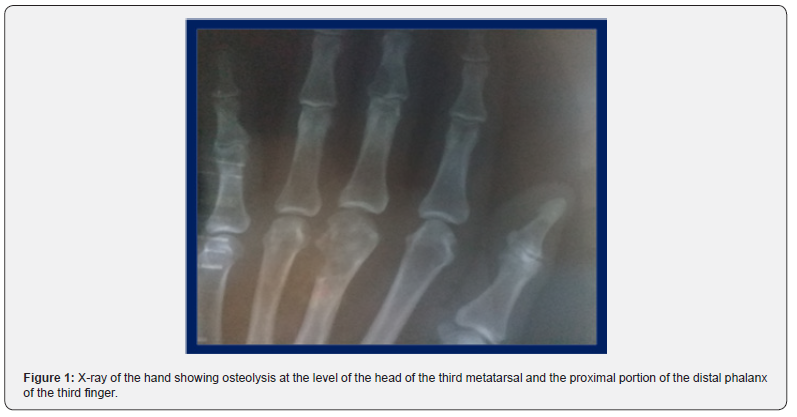

We perform a general and special interrogation and physical examination of both hands. We found no conditions in the general physical examination, but in the special examination of the hands, there are visible and palpable tumors in the right hand, the most striking in the head of the third metatarsal, although they also exist in the distal phalanx of the same finger (Figure 1). We perform complementary hematological and radiological examinations (Table 1). A bone marrow aspiration biopsy was performed, looking for MM, a test that was negative, as was the protein electrophoresis. We performed surgery to excise the lesion and sample for biopsy. Biopsy number B-231.22 at the Mártires del 9 de Abril Hospital and number IHQ-938.22 at the Hermanos Amejeiras national hospital. Biopsy of the bones of the hand - head of the third metacarpal - with clinical diagnosis of bone tumor, immunohistochemical tests are performed.

Plasmacytomas are rare neoplastic tumors, located outside the bone marrow, more frequent in the upper respiratory tract and with a very low frequency retroperitoneal. Between 1905 and 1997 patients between the fourth and seventh decade of life were found; Of 714 cases, 17.8% consisted of extramedullary plasmacytomas [5]. Solitary bone plasmacytoma is a rare plasma cell tumor that has been observed as a precursor to multiple myeloma; It is located mainly in the spine, causing pain at the thoracic and/or lumbar level. Solitary bone plasmacytoma is located mainly in the spine (50% of cases) or in the peripheral long bones. More unusual presentations have been described, such as the coxofemoral joint, chest wall, maxillary sinus, or skull [6]. To make a positive diagnosis of POS requires a series of criteria, firstly histological evidence of a neoplastic mass of plasma cells in a bone. In the case presented, a bone tumor was found that destroyed part of the head of the third metacarpal. In radiological studies carried out in other portions of the body, there are no lytic lesions.